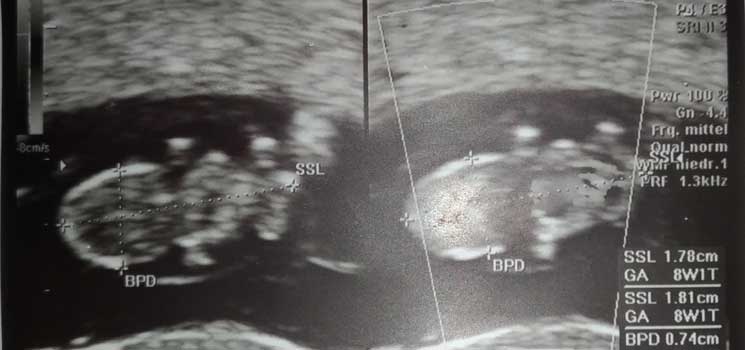

Ein Wunder ist geschehen - Tagebücher aus der Schwangerschaft von Lina aus Traunstein